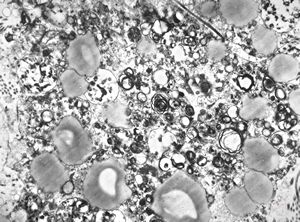

F,68y. | xanthomatous cell in atherosclerotic plaque - a. vertebralis